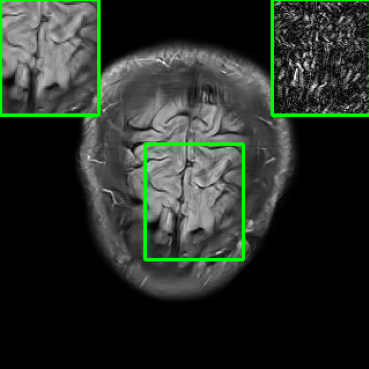

In Fig. 1-(a) and (b), we show reconstructed images using MoDL originating from a benign (i.e., undisturbed) input and a PGD-perturbed input, respectively. It is evident that the worst-case input disturbance significantly deteriorates the quality of the reconstructed image. While one focus of this work is to enhance robustness against input perturbations, Fig.1-(c) and (d) highlight two additional potential sources of instability that the reconstructor (MoDL) can encounter during testing: variations in the measurement sampling rate (resulting in “perturbations” to the sparsity of the sampling mask in ) [21], and changes in the number of unrolling steps [23]. In scenarios where the sampling mask (Fig.1-(c)) or number of unrolling steps (Fig.1-(d)) deviate from the settings used during MoDL training, we observe a significant degradation in performance compared to the original setup (Fig.1-(a)), even in the absence of additive measurement perturbations. In Section IV, we demonstrate how our method improves the reconstruction robustness in the presence of different types of perturbations, including those in Fig.1.

| Ground Truth | Vanilla MoDL | RS-E2E | SMUG |

![]() |

| PSNR = dB | PSNR = 24.84 dB | PSNR = 25.78 dB | PSNR = 30.81 dB |

| AT | Score-MRI | Deep-Equilibrium | Weighted-SMUG |

| PSNR = 30.72 dB | PSNR = 30.21 dB | PSNR = 24.58 dB | PSNR = 31.41 dB |

Results for the FastMRI Brain Dataset: we present the robustness results of the proposed approaches w.r.t. additive noise. In particular, the evaluation is conducted on the clean, noisy (with added Gaussian noise), and worst-case perturbed (using PGD for each method) measurements. Fig. 3 presents testing set PSNR and SSIM values as box plots for different smoothing architectures, along with vanilla MoDL and the other baselines using the brain dataset. The clean accuracies of Weighted SMUG and SMUG are similar to vanilla MoDL indicating a good clean accuracy vs. robustness trade-off. As indicated by the PSNR and SSIM values, we observe that weighted SMUG, on average, outperforms all other baselines in robust accuracy (the second and third set of box plots of the two rows in Fig. 3). This observation is consistent with the visualization of reconstructed images for the brain dataset in Fig. 4. We note that weighted SMUG requires longer time for training, which represents a trade-off. When comparing to AT, we observe that AT is comparable to SMUG in the case of robust (or worst-case noise) accuracy. However, the drop in clean accuracy (without perturbations) for AT is significantly larger than for SMUG. Furthermore, AT takes a much longer training time as it requires to solve an optimization problem (PGD) for every training data sample at every iteration to obtain the worst-case perturbations. Furthermore, we observe that its effectiveness is degraded for other perturbations including random noise as well as modified sampling rates shown in the next subsection. Importantly, the proposed SMUG and Weighted SMUG are not trained to be robust to any specific perturbations or instabilities, but are nevertheless effective for several scenarios.